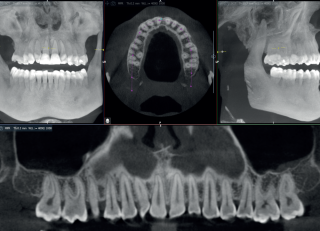

Nowoczesny detektor w Acteon X-Mind Optima 3D zapewnia wyjątkową jakość obrazowania, kluczową w precyzyjnej diagnostyce. Dzięki filtrowi ClearIQ uzyskasz niezwykle przejrzysty obraz, a redukcja artefaktów zbieżnych zwiększy czytelność skanów. Szeroki zakres pól widzenia (5 x 5 – 17 x 12 cm) umożliwia diagnostykę w ortodoncji, chirurgii ortognatycznej, implantologii, czy leczeniu skomplikowanych przypadków ortognatycznych. Rozszerzony zakres napięcia lampy do 90 kV pozwala na lepszą penetrację tkanek, co przekłada się na jeszcze wyraźniejsze detale anatomiczne.

X-Mind Optima 3D to przełom w dziedzinie diagnostyki CBCT. Unikalne oprogramowanie RealGuide™ 5.4 w urządzeniu, napędzane mocą AI, usprawnia skomplikowane procedury diagnostyczne i implantologiczne. Wykorzystane algorytmy automatyzują kluczowe procesy oraz ułatwiają wykonywanie złożonych zabiegów. W rezultacie aparat stanowi nieocenioną pomoc m.in. w segmentacji zębów, wykreślaniu CPR, śledzeniu przebiegu nerwów i pozycjonowaniu implantów.